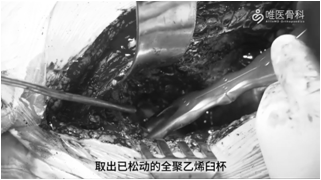

取出髋臼假体:去除髋臼周围的瘢痕组织,显露整个髋臼缘,取出已松动的全聚乙烯臼杯。然后用刮勺刮除纤维膜,充分显露骨床,评估残余骨量。根据髋臼内侧壁、前后壁及臼顶的骨缺损程度以及髋关节中心上移程度确定骨缺损分型。本病例髋臼骨缺损分型为:Paprosky ⅡC型。